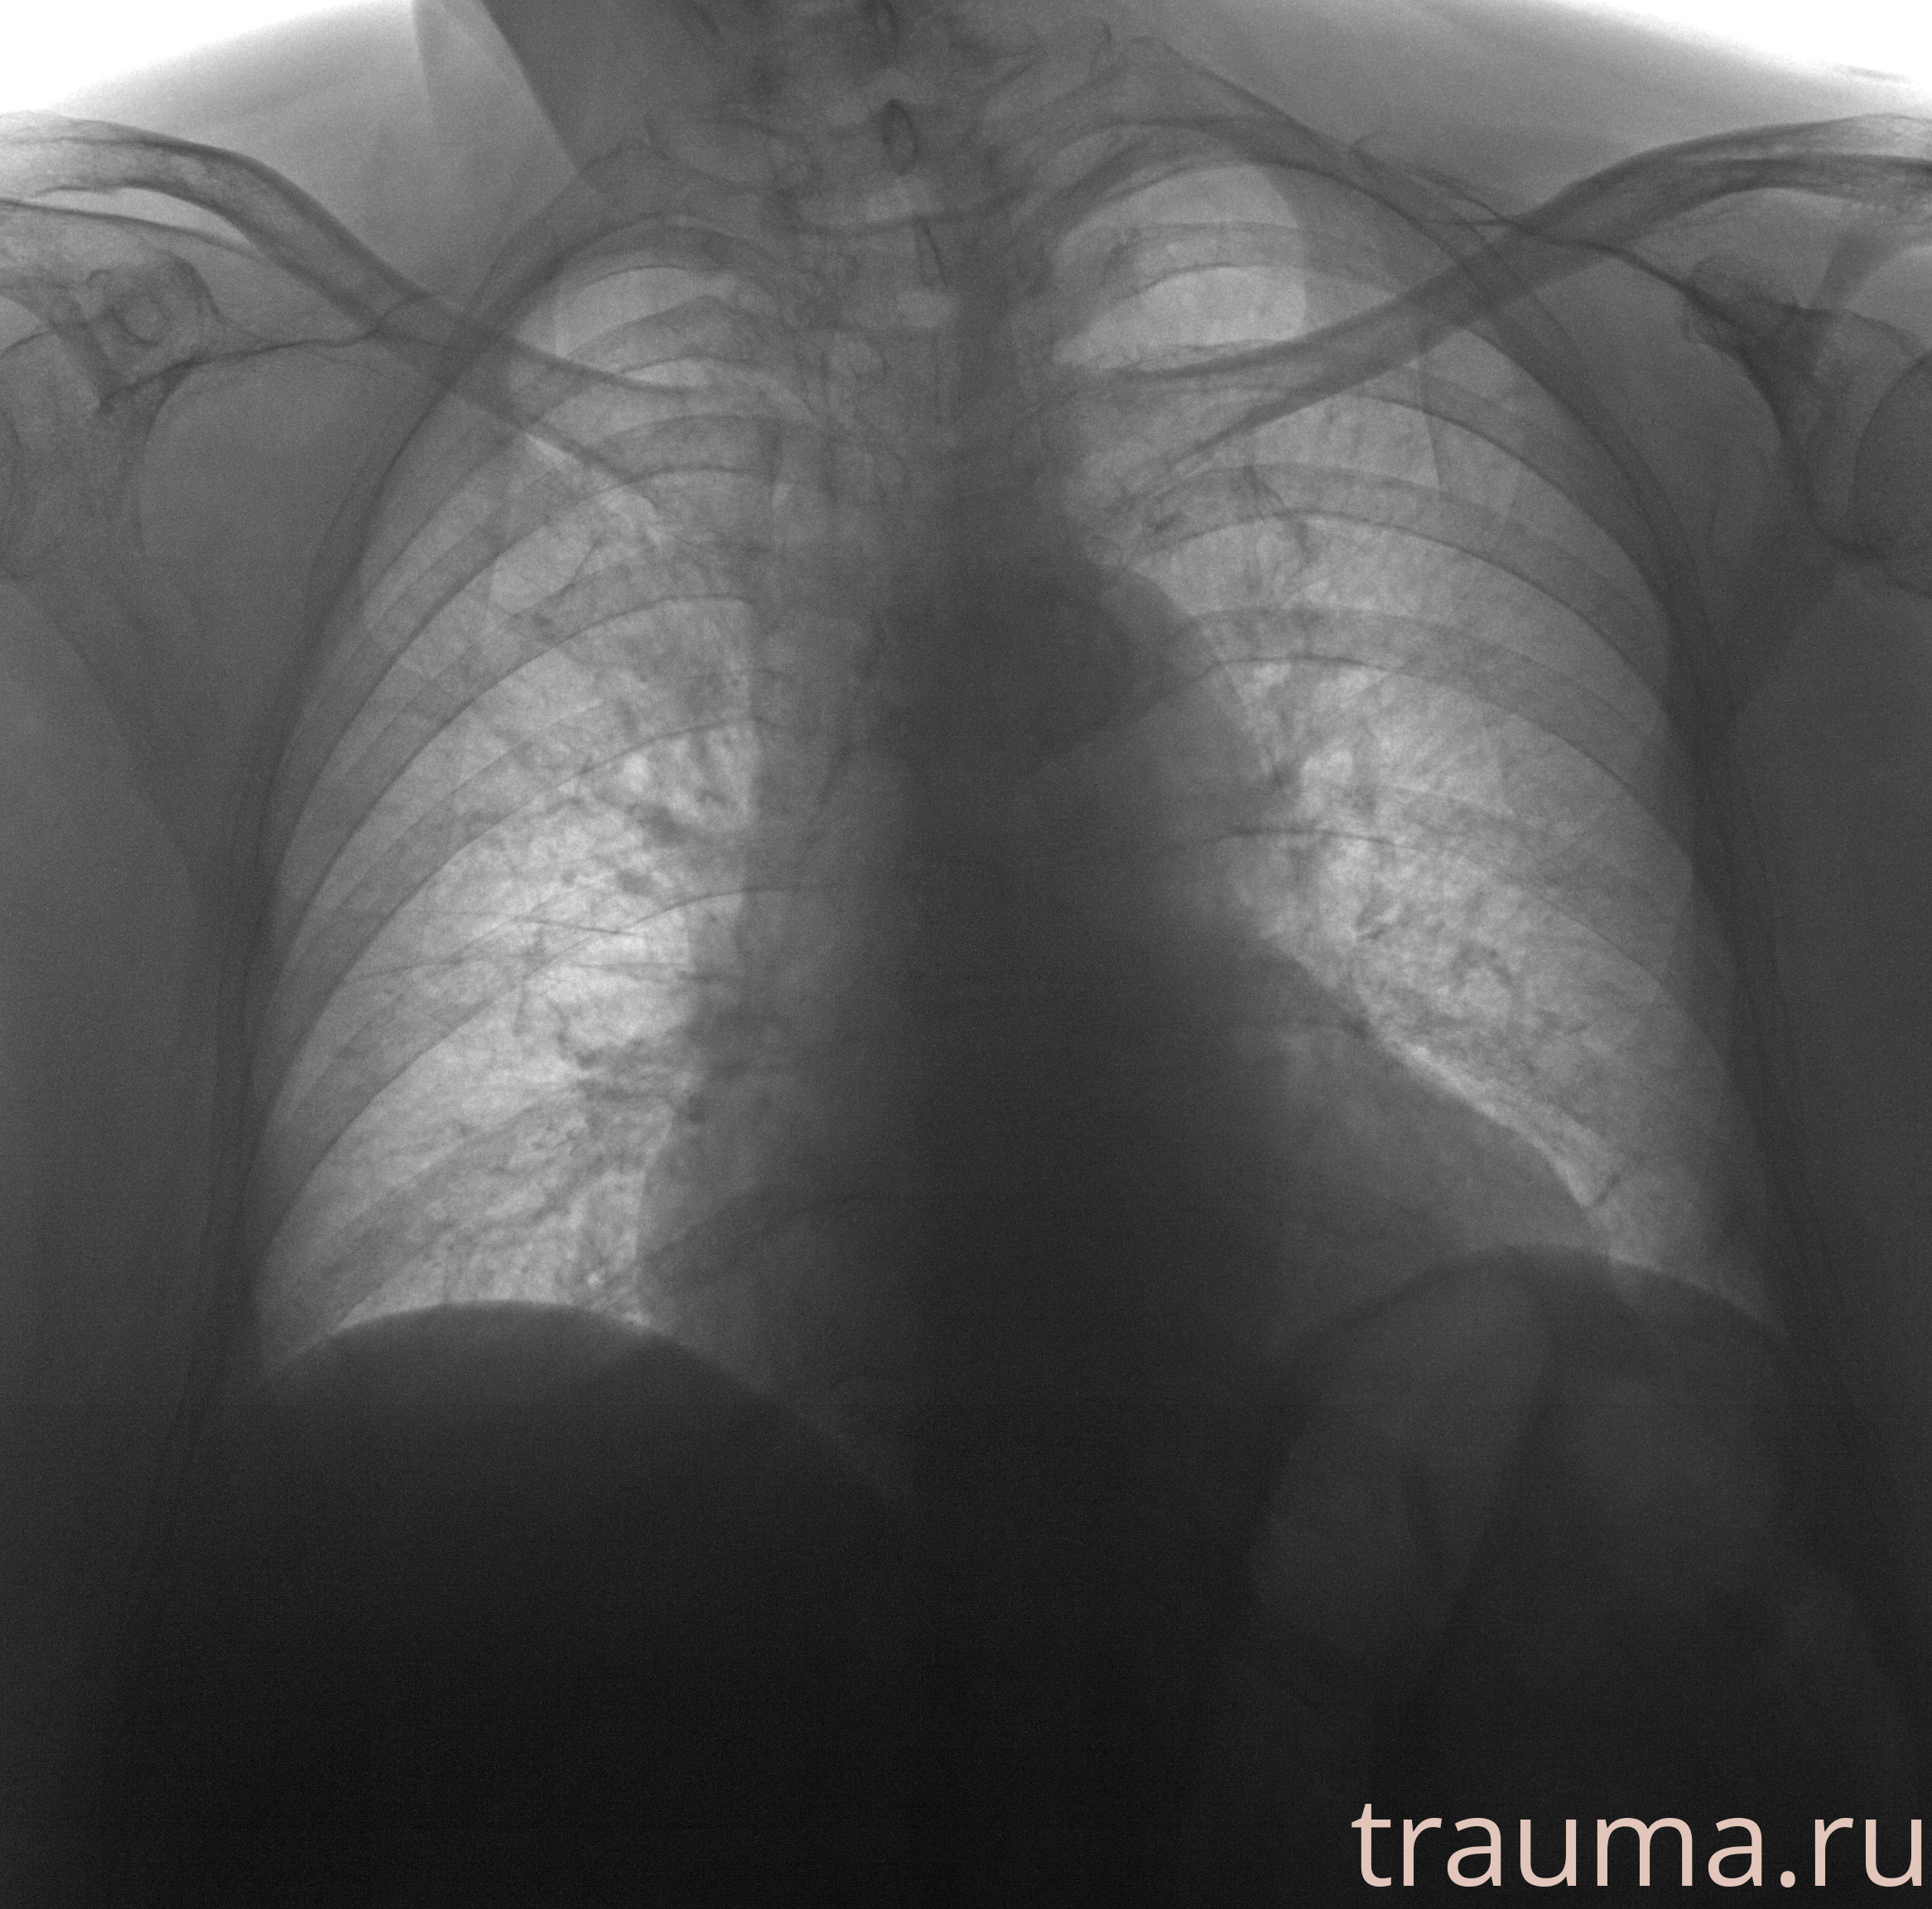

Рентген на дому: по вашему адресу приезжает врач-рентгенолог, травматолог-ортопед с мобильным рентгеновским аппаратом, проводит диагностику травмы или заболевания, делает необходимые рентгенограммы, дает рекомендации по дальнейшему лечению. Получить качественные снимки в домашних условиях возможно благодаря уникальной методике, разработанной МосРентген Центром для института  Склифосовского

при переломе шейки бедра и пневмонии от компании МосРентген Центр - партнера Института имени Склифосовского